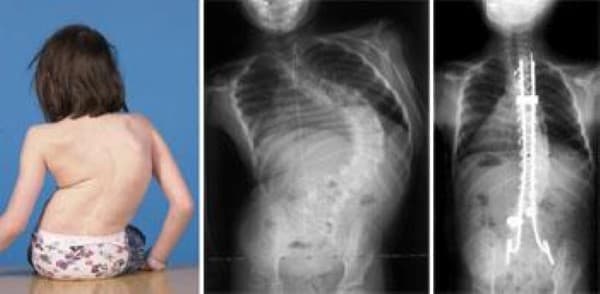

Pediatric Spine Problems